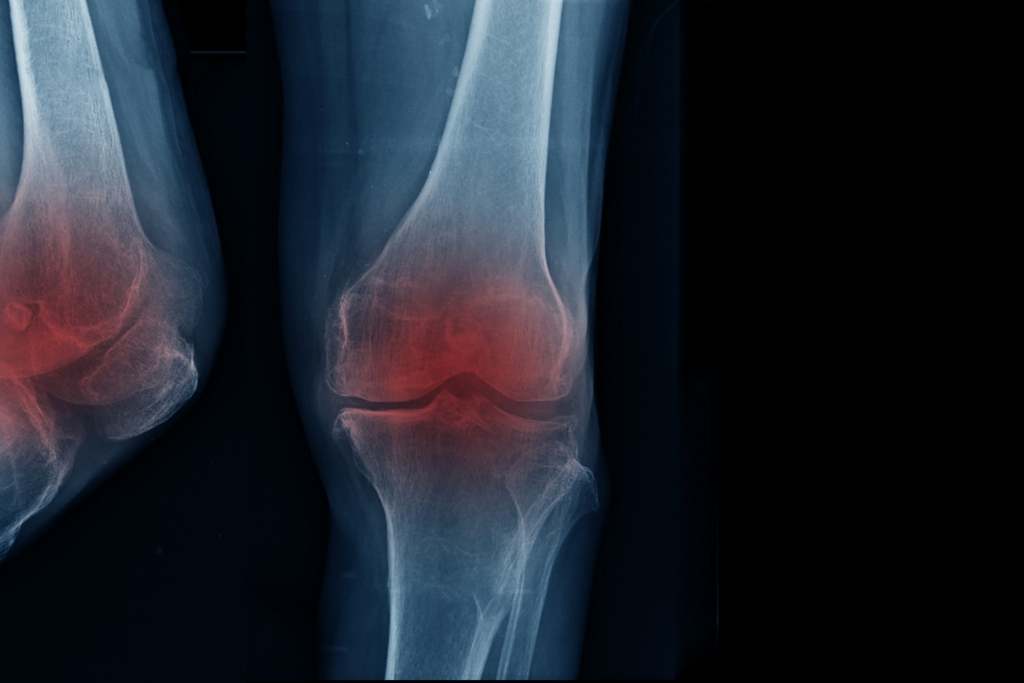

Is Non-Surgical Treatment Possible for Knee Osteoarthriti?

Is a Non-Surgical Solution Possible for Knee Osteoarthriti?

Stating that knee prosthesis surgeries, which have been applied in knee and joint problems for more than fifty years, as well as non-surgical treatments that can be applied give successful results, Dr. Özgür Oktay Nar said: “Knee replacement surgery is a successful treatment method that we have been applying for years, especially for knee arthritis. In the knee prosthesis application performed using anesthesia, it is aimed that our patients can move more comfortably with the artificial joint placed in the knee. However, surgery lasting 1.5 hours for an average knee, the psychology of anesthesia and the physical therapy processes afterwards can cause anxiety in our patients. With the latest technologies, non-surgical solutions have started to be applied in knee arthritis and high success rates have been achieved. In this context, yes, there are very successful non-surgical methods in knee arthritis and we can apply them. For example, New Generation Hydrogel Treatment is a successful application that does not require surgery in the treatment of knee arthritis and is applied in as little as 10 minutes and provides relief to our patients.”